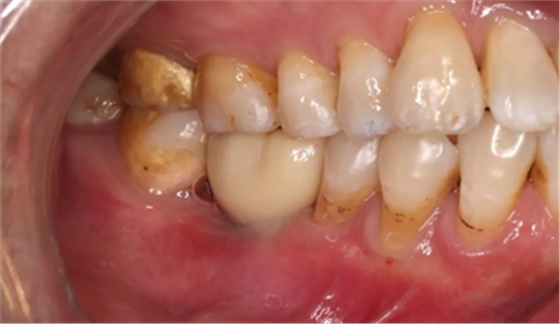

2、术前口腔内照片

46牙烤瓷冠修复,牙周红肿,叩痛,松2度。骨吸收波及邻牙,邻牙牙周情况不佳,45牙松2度,47牙松1度。

(摄于2016年8月31日,反光板协助拍摄)